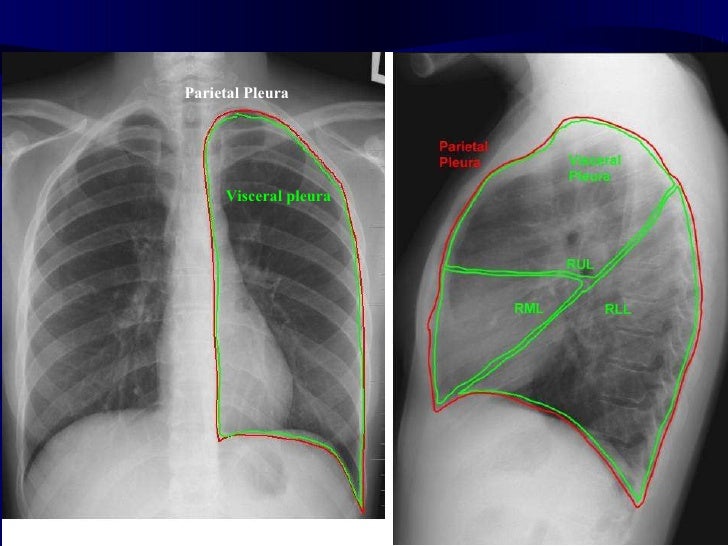

Pulmonary Imaging

pulmonary